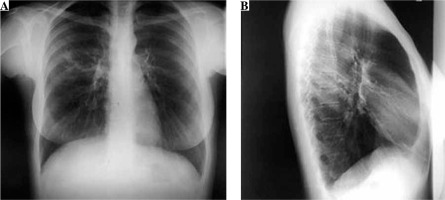

A 31-year-old woman was admitted to the hospital for the treatment of newly diagnosed drug-resistant (pre-extensively drug resistant) pulmonary tuberculosis (chest X-ray at time of diagnosis – Fig. 1). She was treated with second-line antituberculosis drugs: moxifloxacin, kanamycin, cycloserine, prothionamide, para-aminosalicylic acid. After 3 weeks of therapy she developed high fever (> 39°C), lymphadenopathy in the cervical and axillary regions and pruritic maculopapular eruption all over the body (Fig. 2). Hematologic abnormalities such as leukocytosis with eosinophilia (1.81 × 109/l) and monocytosis (1.85 × 109/l) were detected in peripheral blood of the patient. Hepatitis was asymptomatic and detected by the evaluation of liver function: serum aspartate aminotransferase (AST) 1379 IU/l and alanine aminotransferase (ALT) 1221 IU/l; levels of liver enzymes were increased by approximately 30-40-fold above the normal limits. The positive diagnosis of Epstein-Barr infection was based on the onset of increase in the anti-Epstein-Barr immunoglobulin (Ig) G titer (> 200 U/ml), implicating Epstein-Barr virus re-activation. Based on the clinic and laboratory findings diagnosis of DiHS/DRESS was suspected, and all the drugs were discontinued. Symptoms and laboratory abnormalities gradually resolved over 4 weeks without additional treatment.

Fig. 1

Chest X ray posterior-anterior view (A) and right lateral view (B) on admission. On the superior lobe posterior segment of the right lung a mild parenchymal opacity with several nodules can be seen